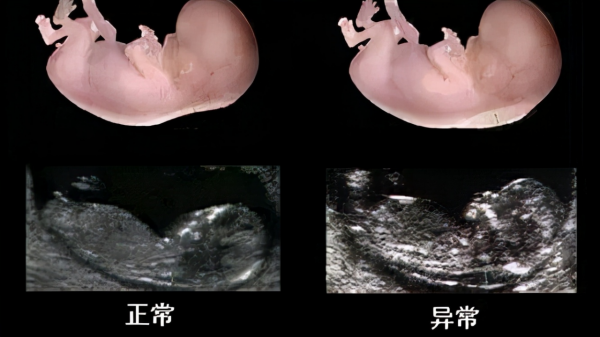

- 生理狀態:正常情況下,在母體內胚胎時期,每節椎骨由3個原發性骨化中心所構成,即椎體骨化中心、椎弓.根和椎弓骨化中心(左右兩塊)。在椎體骨化中心的中央部分有一條在胚胎早期遺留下來的脊索痕跡,在胚胎髮育過程中,這條位於椎體中央部位的脊索痕跡逐漸消失,而相當於椎間盤部位的脊索痕跡向左右兩側擴充套件,形成椎間隙。這樣就產生了具有-連串椎體和椎間盤的 脊柱形態。

- 病理狀態:如果單側(左 側或右側)半椎體骨化中心發育障礙或不發育,而另一側骨化中心正常發育,則可能形成半椎體畸形。脊柱雙側不對稱生長,即雙側生長速度不同。其生長速度差異越大,側凸的進展越快, 程度也會越嚴重。